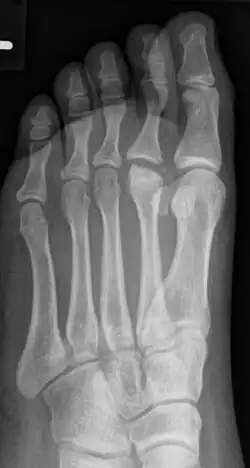

Der betroffene Vorfuß schmerzt bei Belastung, gelegentlich treten auch Schwellungen am Fußrücken im Bereich des Mittelfußköpfchens auf. Im Röntgenbild zeigen sich erst eine Veränderung in der Knochenstruktur des betroffenen Mittelfußköpfchens und erst später eine Abflachung und eine Verbreiterung (siehe Abbildung). Auf Dauer kann die Fehlform der Mittelfußköpfchens zu einer Arthrose führen.